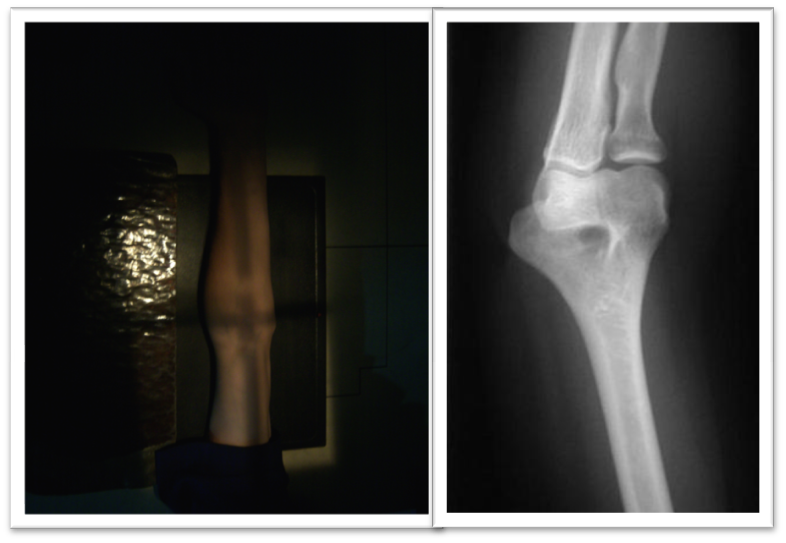

Source: rxconvencional.blogspot.com

Rmn De Codo - Web en la resonancia magnética de codo, se obtienen imágenes de las partes blandas, articulaciones o el hueso del. Web la epicondilitis lateral, también conocida como codo de tenista, es un síndrome por sobreuso del tendón extensor común y. Web rm de codo. Web la rm es la técnia de elección en la valoración del codo doloroso ya que ofrece.